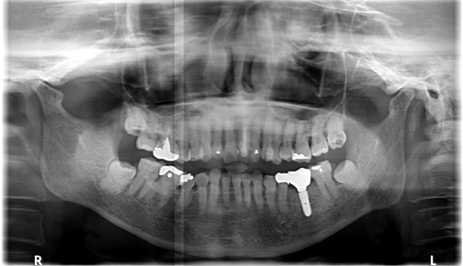

インプラント6本埋入+FGG(60代女性)

治療前

治療後

施術名 | インプラント6本埋入+FGG |

主訴 | 噛めない |

施術の副作用(リスク) | 脱落感染 |

施術の価格 | 施術の費用 1本GBR5万~10万(税抜き)+インプラント埋入補綴まで35万(税抜き) |

コメント | 下の前歯は再生療法ブリッジを行い歯を保存しました |